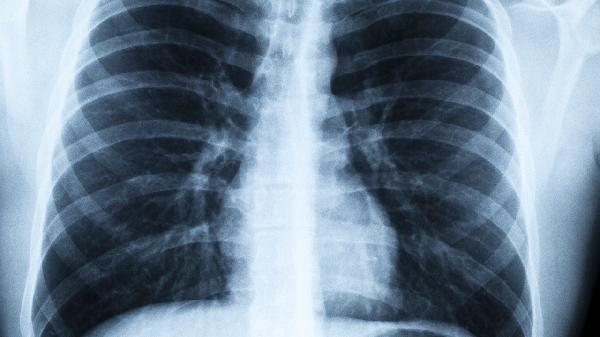

尘肺病是由于长期吸入生产性粉尘并在肺内潴留引起的以肺组织弥漫性纤维化为主的疾病,主要治疗方法是脱离粉尘环境、药物治疗和氧疗。尘肺病的病因与职业暴露密切相关,常见于矿工、建筑工人等长期接触粉尘的工种。粉尘颗粒进入肺部后,引发炎症反应,导致肺组织纤维化,影响肺功能。长期暴露在粉尘环境中,肺部的防御机制无法完全清除这些颗粒,逐渐形成病变。

5、病理过程:粉尘颗粒进入肺部后,肺泡巨噬细胞试图吞噬这些颗粒,但无法完全清除。长期积累导致慢性炎症反应,肺组织逐渐纤维化,最终影响肺功能。病变从轻度炎症发展为重度纤维化,严重时可能导致呼吸衰竭。

治疗方法包括脱离粉尘环境、药物治疗和氧疗。脱离粉尘环境是首要措施,避免进一步吸入粉尘。药物治疗包括使用糖皮质激素减轻炎症,抗氧化剂如N-乙酰半胱氨酸减少氧化应激,以及支气管扩张剂改善呼吸困难。氧疗适用于低氧血症患者,通过吸氧改善氧合。肺康复训练和呼吸功能锻炼也有助于改善肺功能。定期进行肺功能检查和影像学监测,及时发现病情变化,调整治疗方案。